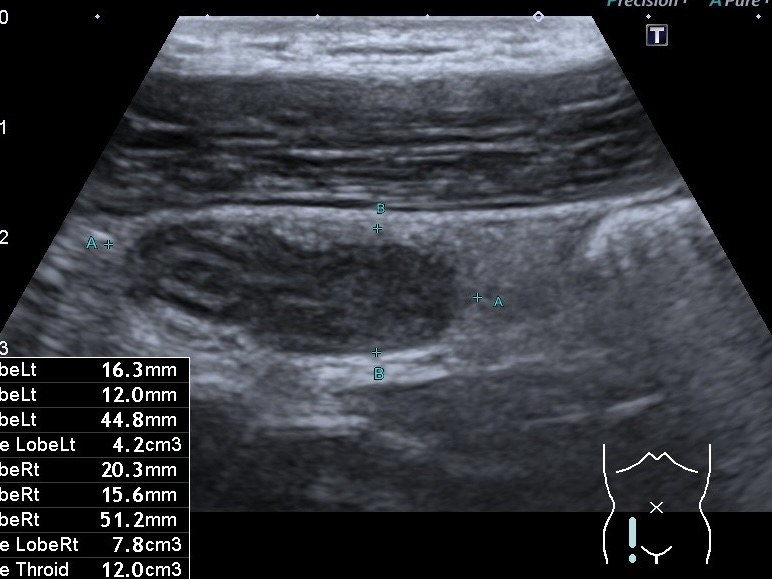

На знімках представлений випадок гострого апендициту у молодого чоловіка. Біль при цьому був не сильний, за словами пацієнта, він ходив із ним протягом 5 днів. При цьому пацієнт звертався до гастроентеролога в приватну клініку, і під час обстеження лікар не виявив ознак гострого апендициту. Проте лікар призначив УЗД органів черевної порожнини.

Під час УЗД було виявлено збільшений апендикс із ще збереженою пошаровою структурою, який не стискався при компресії датчиком і був болісним при натисканні. Навколо відзначалася змінена жирова клітковина та збільшені мезентеріальні лімфатичні вузли. Пацієнта того ж дня було направлено до хірурга та прооперовано. Хірург підтвердив, що вже мав місце флегмонозний апендицит.